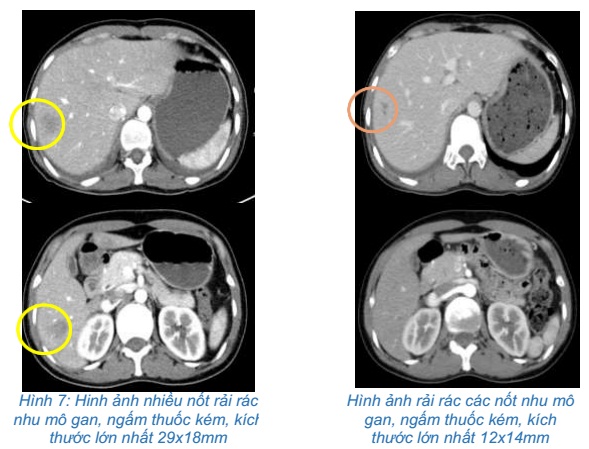

- Chụp cắt lớp vi tính ổ bụng:

Hình 2: Hình ảnh cắt lớp vi tính ổ bụng: hình ảnh nhiều nốt rải rác nhu mô gan, ngấm thuốc kém, kích thước lớn nhất 29x18mm (vòng tròn vàng).

- Chụp cắt lớp vi tính bụng: Rải rác các nốt nhu mô gan, ngấm thuốc kém, kích thước lớn nhất 12x14mm

So sánh hình ảnh cắt lớp vi tính bụng trước và sau điều trị 3 chu kỳ: